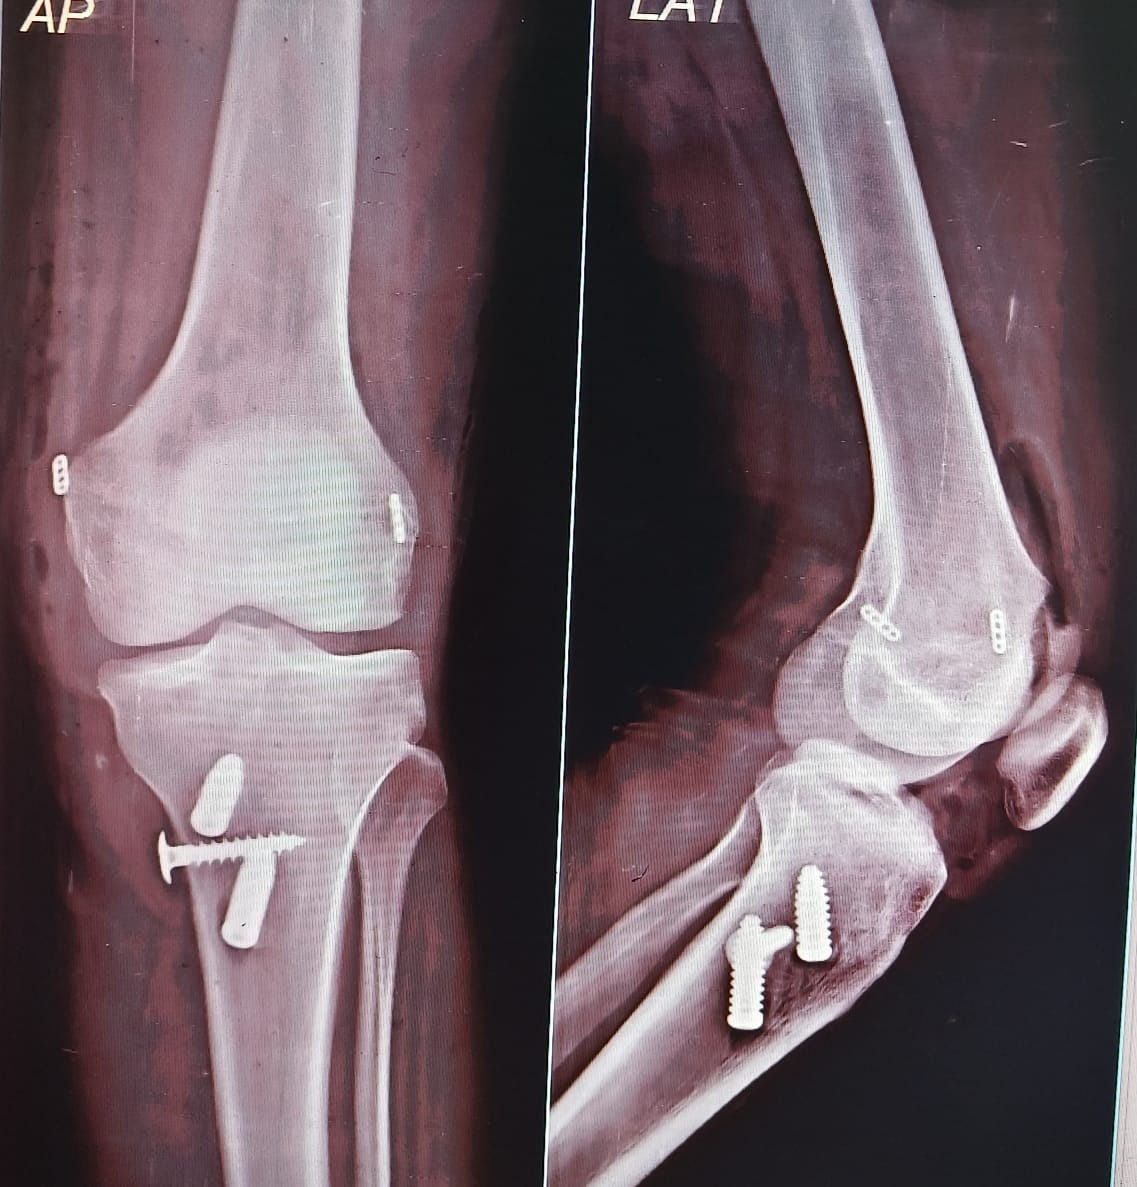

Multi ligament Knee surgery

Multi-ligament knee reconstruction is a complex surgical procedure aimed at repairing multiple torn ligaments in the knee joint, often resulting from high-energy trauma such as motor vehicle accidents or severe sports injuries. This surgery is essential for restoring knee stability and function, preventing long-term complications like osteoarthritis